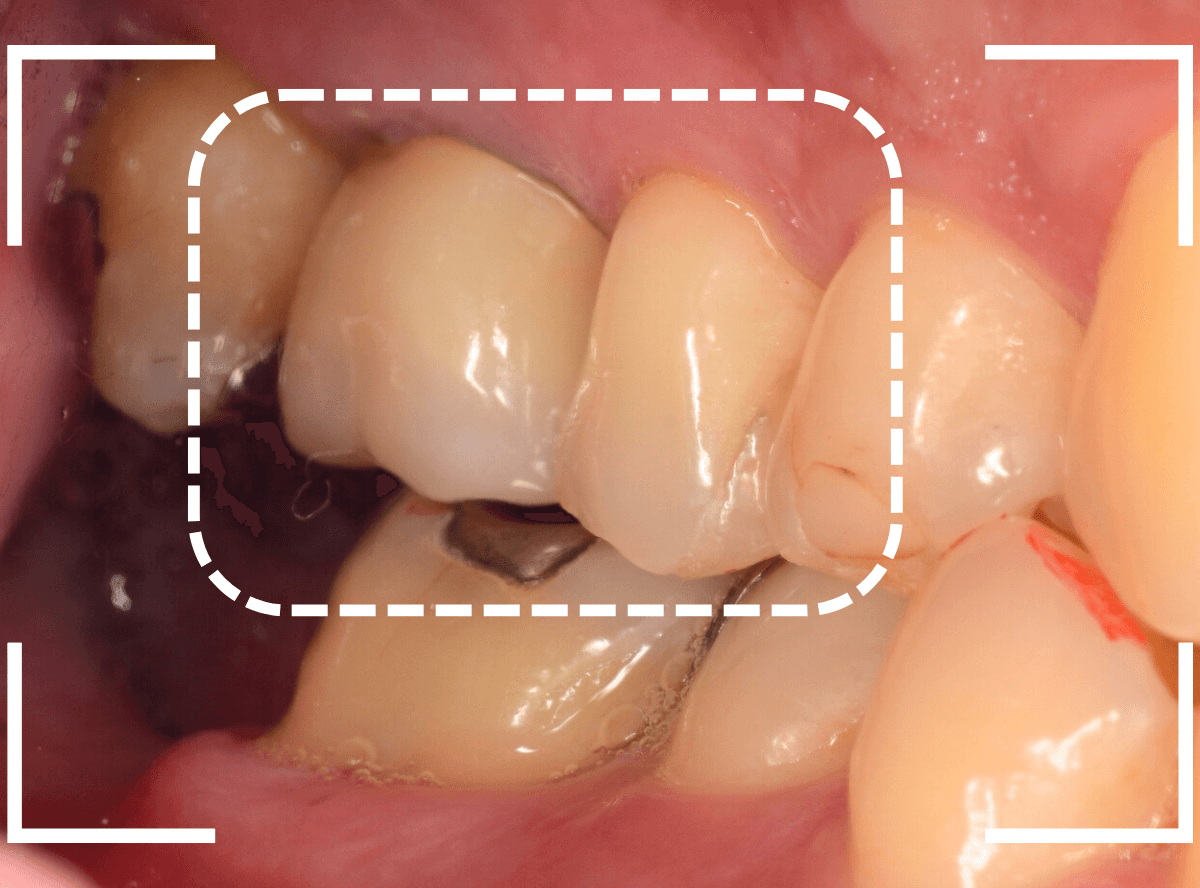

Case.17 虫歯治療後、オール・ジルコニア・クラウンとE-MAXで修復

今回は、奥歯が神経に達する虫歯になってしまった患者さんのケースです。

隣りの歯とのすき間に大きな穴が空いているのが見えます。

レントゲン写真で確認します。

金属のつめものの下が、神経まで達する大きな虫歯になっています。

麻酔をして神経の治療をします。

さて、神経の治療が終わり、歯の土台を作ったところで、手前の歯の側面にも虫歯が見つかり、治療を始めました。

手前の歯の虫歯も金属の中まで虫歯になっていました。

手前の歯の虫歯もかなり広い虫歯でした。

ここで、両歯とも白い歯の治療を希望されましたので、E-MAXインレー、オールジルコニアクラウンで治療する事になりました。